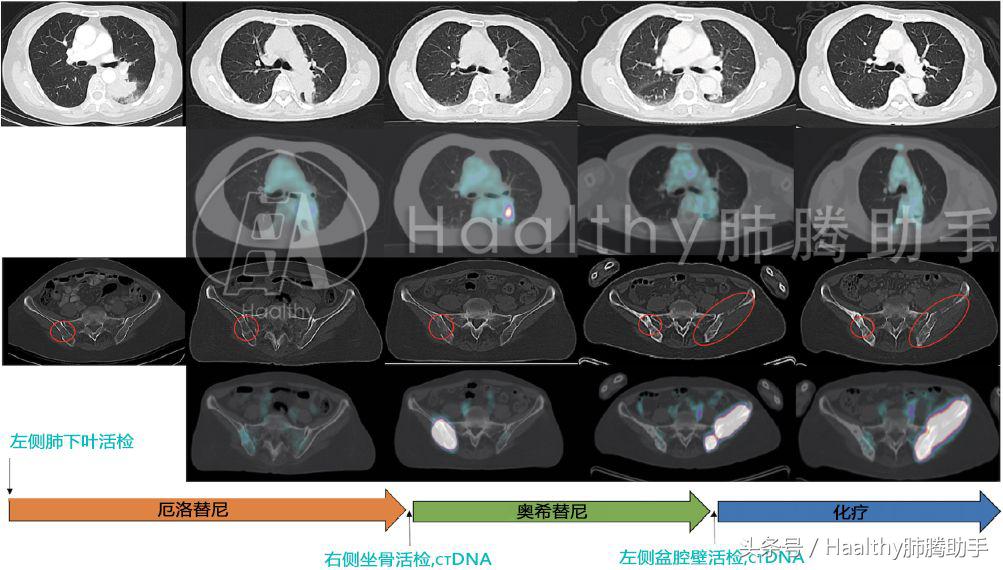

患者是一名69岁亚裔女性,从未吸烟,2014年7月因背部和臀部疼痛进行检查,发现左下肺叶肿瘤,右侧坐骨有转移灶,通过CT引导活检左下肺叶肿瘤确诊低分化肺腺癌,有EGFR L858R突变,T790M阴性。患者接受厄洛替尼治疗,疾病部分缓解,症状改善。

患者持续应用13个月厄洛替尼后左下肺叶出现新病灶,骨转移也再次进展。患者再次进行活检,这次是对右侧盆腔软组织转移瘤进行活检,同时又用血液进行了ctDNA检测。

据此患者于2015年11月开始接受奥希替尼治疗,疾病再次缓解,症状改善。

患者靶向治疗耐药后都进行了组织活检和ctDNA检测,如下图所示:

患者接受12个月奥希替尼后又再次耐药,左侧盆腔出现新发病灶并累及骨质,医生对患者左盆腔软组织转移瘤进行再次活检,同时也进行了ctDNA检测。

由上图可知:患者的组织活检和ctDNA结果均显示EGFR L858R突变,T790M和G796S顺式突变,这是新发现的奥希替尼耐药突变。然而目前我们并不知道如何治疗这种耐药突变,稳妥起见医生决定为患者施行培美曲塞+卡铂的化疗方案。